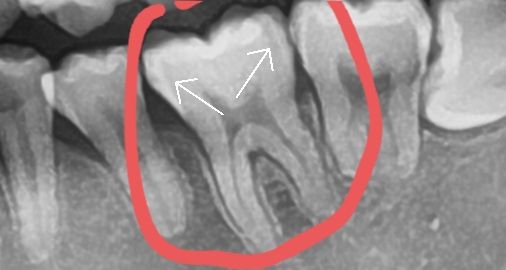

제가 표시해놓은부분이 충치가 맞나요?

저는 전혀충치같아 보이지않는데도 선생님께서 팔수록 깊다고하셔서 인레이 했습니다만 다른 치과선생님들께서는 파노라마 보시기에 어떻게 생각하시는지요

사진 상으로 보았을 때는 충치 자체가 있습니다. 다만 이것이 얼마나 깊은지는 치료를 하면서 알 수 있습니다. 해당 사진은 3차원을 2차원으로 옮겨 놨기 때문에 구조물이 겹쳐 보여 충치 진단에 한계가 있습니다.

x-ray 상에서 인접면 충치(사이 충치)가 확인됩니다. 인접면 충치는 안쪽으로 깊이 진행되는 경우가 많습니다.

엑스레이 상으로 보면 인접면에 충치가 있어 보입니다. 양쪽다 충치가 있으신거 같습니다.

그 치아의 사진상 왼쪽 부위에 충치가 있습니다.

방사선 사진에서 해당 음영을 충치로 확정짓기에는 다소 어려움은 있습니다. 치아 구조상 음영이 질 수 있는 부분이고 충치와 겹쳐있는 경우는 감별이 쉽지 않습니다. 치과의사분께서 실제로 치료를 하면서 보셨을테니 충치가 있어 제거가 필요한 부분을 잘 파악하셨을 것입니다.

현재 사진상으론 표시하신 부위보다 바깥으로 검게 얼룩이 있는 부분이 충치였던 것으로 판단됩니다

방사선상 음영이 약간 보이기 때문에 충치가 진행되고 있는 것으로 의심해 볼 수는 있습니다.

하지만 방사선상 음영이 있다고 반드시 충치가 있는 것은 아니고 육안으로 한 번 더 확인을 해야 정확하게 알 수가 있습니다.